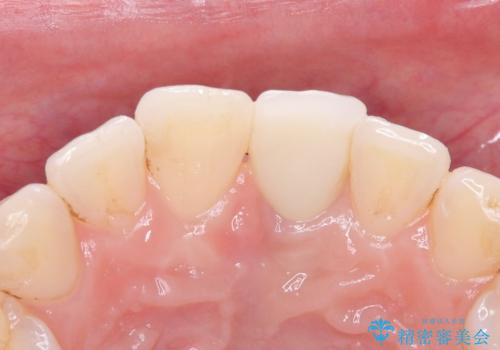

- 歯頚部外部吸収により抜歯適応の歯を抜歯して即時にインプラントを埋入したケースです。

歯肉が下がっていることを気にされていたため、できるだけ考慮して術式を決めて治療を行いました。

インプラントの手術は二回になることが多いですが、1Dayインプラントの場合は手術は一回で済みます。